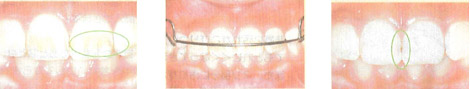

例)その1:白色

これは初期虫歯です。

これ以上進行させないためにハミガキをがんばってフッ素を塗って予防しましょう。